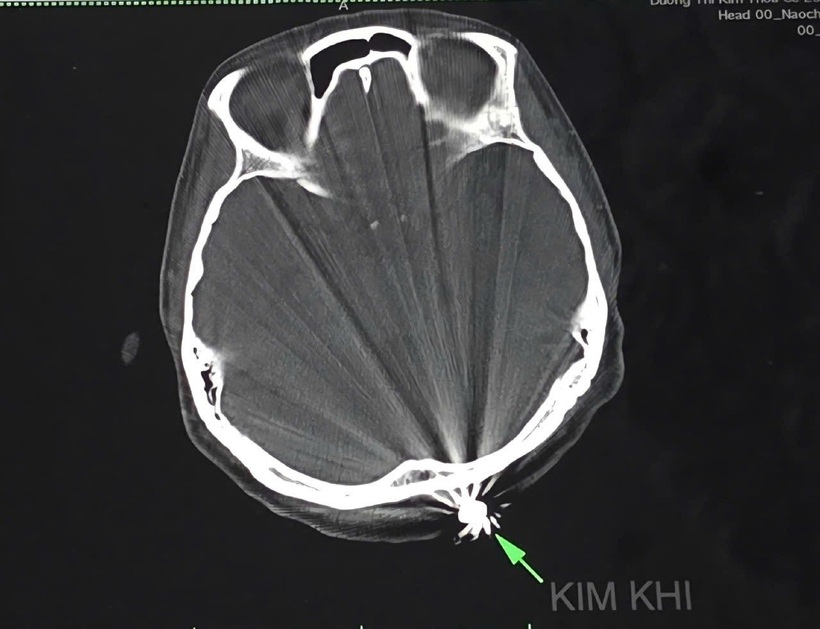

Hình kim khí (viên đạn) trên phim chụp cắt lớp vi tính. Ảnh: Dân Trí

Sau khi hội chẩn, các bác sĩ khoa ngoại Thần kinh đã quyết định tiến hành phẫu thuật lấy dị vật và xử trí tổn thương. Mở rộng vết mổ khoảng 3cm lấy ra dị vật kim khí hình đầu đạn 0,5x0,3cm.

Đáng chú ý, viên đạn chỉ xuyên qua lớp da, chạm nhẹ vào xương chẩm, không gây tổn thương nghiêm trọng đến não và cấu trúc lân cận. Đây là một trường hợp được đánh giá là may mắn và hiếm gặp.